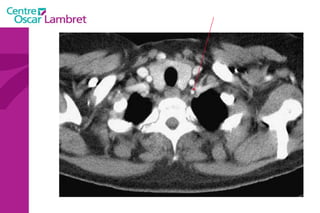

Les  3 troncs supra aortiques  naissent sur la portion horizontale de la crosse de l’aorte : Le tronc Artériel Brachio-céphalique. L’artère Carotide commune gauche. L’artère sus-clavière gauche. Tous ont une branche à destinée céphalique. L’appareil circulatoire

Les Troncs Supra Aortiques s’organisent autour de la trachée à leur origine. L’appareil circulatoire

Le  Tronc artériel Brachio-céphalique  : Naît de la face supérieure du 2e segment horizontal de la crosse aortique à hauteur de T 4. Volumineux, (diamètre 12 mm - longueur 3 cm) il se dirige en haut et à droite croisant la partie droite de la trachée. Derrière l’articulation sterno-claviculaire droite il bifurque en artères sous-clavière droite et carotide primitive droite.  L’appareil circulatoire